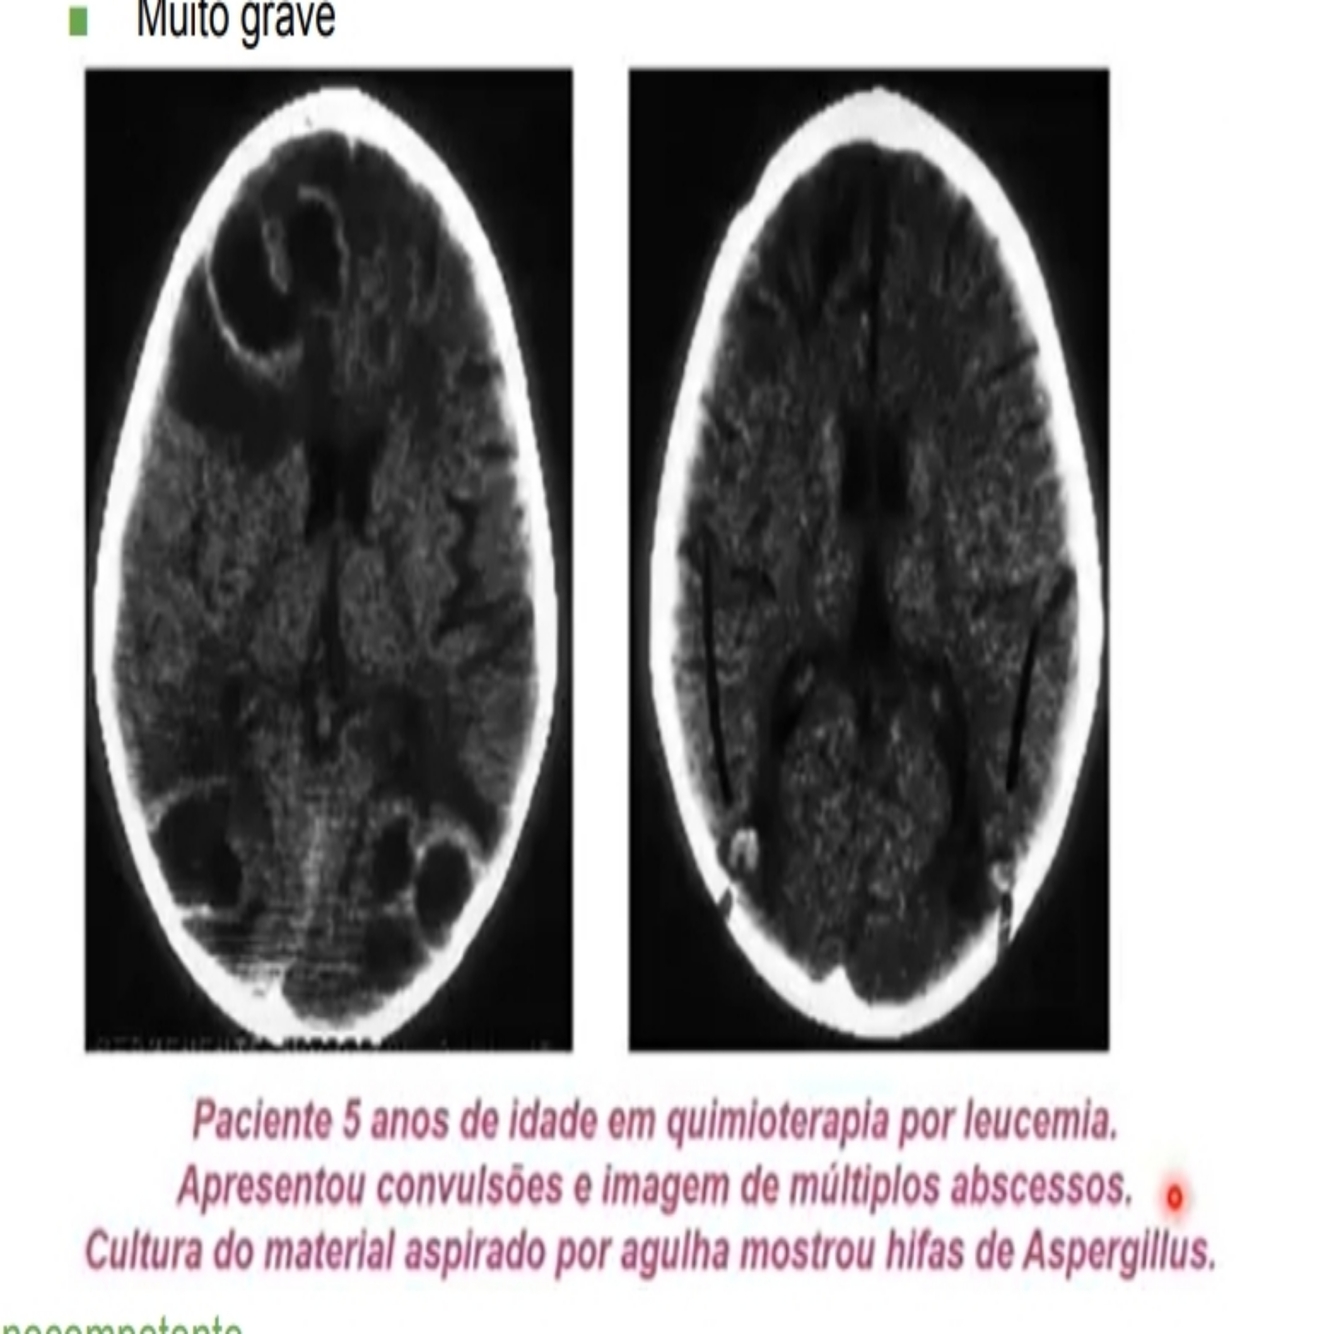

Acometimento do SNC

• alterações de nivel de consiencia

• convulsoes

• deficit motor